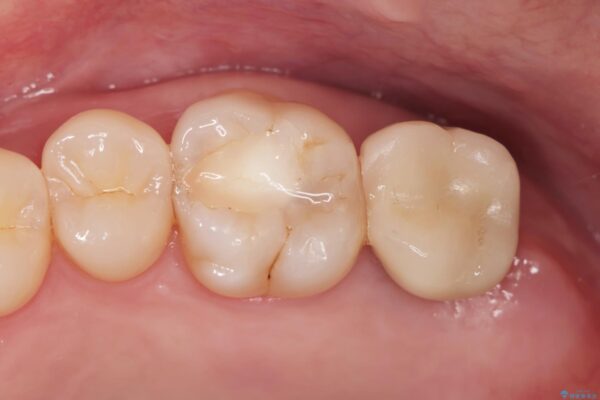

治療を終えて

歯の破折で抜歯を余儀なくされ、ショックが大きかったですが、しっかりとインプラントで咬合機能が回復することができ、喜んでいただくことができました。

治療後

【噛むと歯が疼く】歯牙破折からのインプラント治療 治療後画像 【噛むと歯が疼く】歯牙破折からのインプラント治療 治療後画像 【噛むと歯が疼く】歯牙破折からのインプラント治療 治療後画像 【噛むと歯が疼く】歯牙破折からのインプラント治療 治療後画像